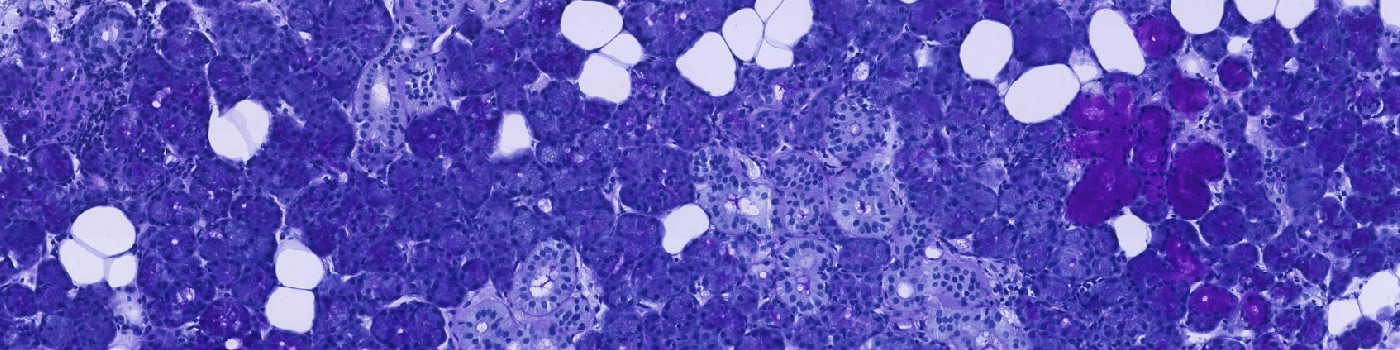

Salivary glands stained with CKAE1/AE2. The blue ROI shows automatic detection of glandular region.

The protocol works on a virtual double stain (VDS) of PAS and CK AE1/AE2 stained serial sections. Initially, the outer boundary of the glandular area is outlined by thresholding the brown feature HDAB-DAB of the CKAE1/AE2 slide. FIGURE 1 and 2 show the aligned sections with outline. In case of artefacts, such as tissue folds etc., the outline should be manually corrected.